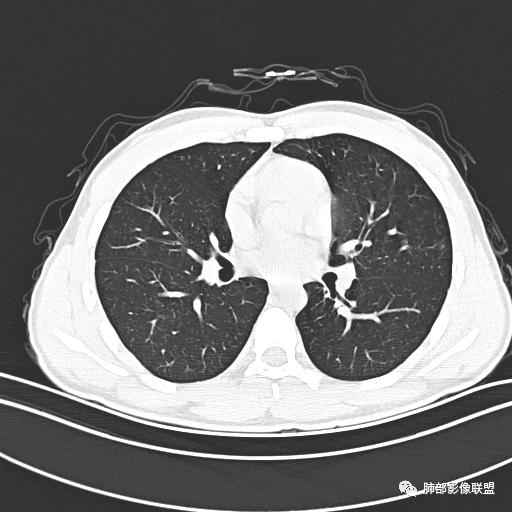

小强:青年,发热,皮疹;双肺散在结节,周围磨玻璃,点晕征,疱疹病毒感染,鉴别荚膜组织胞浆菌,结核。 大雄:青年,急性起病,发热伴全身皮疹2天,抗病毒治疗体温有下降。双肺随机分布大小不等类圆结节,“点晕征”。考虑水痘-疱疹病毒(VZV)血播询问接触史,查体皮疹分布以及形态基本可诊断。 王开金江津中心医院呼吸科:青年男性,起病急,病程短,以发热,皮疹为首发症状,感染指标以单核细胞升高为主,胸部ct双肺多发结界,周围有晕,点晕表现,随机分布,同意於老师意见,水痘疱疹病毒血流感染累及肺。 王秀仙:双肺多发大小不等结节,周围有晕,边缘模糊,呈点晕征表现。青年,急性起病,发热伴全身皮疹2天,抗病毒治疗体温有下降。考虑疱疹病毒。鉴别荚膜组织胞浆菌。 傅昌瑜:19岁男性,发热、全身皮疹2天,单核细胞增高,双肺多发结节,结节边缘见边界不清磨玻璃影。点晕征+发热、全身皮疹+单核细胞增高——考虑水痘-带状疱疹病毒肺炎。 一切∮随缘:年轻男性,发热,皮疹两天,实验室,CRP,PCT增高,影像:双肺多发散在磨玻璃结节,边界欠清,大小不等,呈点晕征改变,以血管束周围分布为主,局部血管束略增粗,其它无明显改变,考虑:1:病毒性肺炎(水痘疱疹病毒?不知道皮肤有无改变)2:真菌(组织胞浆菌,血管侵袭性肺曲霉)3:GPA4:寄生虫(实验室没有看到嗜酸细胞增高) 赵山河:双肺散在结节,周围有晕,边缘模糊,呈点晕征表现。青年,急性起病,发热伴全身皮疹2天,抗病毒治疗体温有下降。考虑水痘—疱疹病毒感染。洪桥爱:青年男性,发热、皮疹2天,伴瘙痒,皮疹于面部首发,之后进展至全身,虽然没有对皮疹进行描述,但是从出疹时间及皮疹进展情况,伴瘙痒,应该就是个水痘患者;CT提示双肺随机分布结节影,部分结节伴有边界不清晕征,考虑水痘血播肺。 刘强:年轻男性,急性起病,皮疹,发热,抗感染治疗体温下降,说明有效。影像表现为散在点晕征,感染类疾病谱(疱疹病毒,真菌,结核),结合年龄,皮肤皮疹,考虑水痘-疱疹病毒性肺炎。 小兜:男性,19岁,发热皮疹两天,颜面部至全身,CRP,降钙素及单核增高。CT示双肺散在小结节,周围伴磨玻璃影,点晕征,考虑为水痘-带状疱疹病毒(varicella-zoster virus,VZV)肺炎 必有路:青年,皮疹+发热+“点晕征”→水痘-疱疹病毒(VZV) 许慧良:青年男性患者,发热、皮疹2天,体温最高38.5℃,第3天皮疹扩展至全身,伴瘙痒,胸部CT:双肺多发随机分布的小结节,结节周边见边界模糊的晕征,考虑水痘病毒感染流心明智:男,19,急性起病,发热伴全身皮疹2天。出疹顺序头→全身,抗病毒有效。胸部CT:两肺多发大小不等类圆形实性小结节影,随机分布,结节周围环绕GGO,边界模糊,呈点晕征。出疹特点是关键,未提示。考虑:血播病毒性肺炎,水痘-疱疹病毒?麻疹?鉴别荚膜组织胞浆菌、TB、血管炎、寄生虫等。 浪迹天涯:病灶多为5-10mm大小结节,结节周围可见磨玻璃样的晕环,常多发,可分布于肺内任何区域,考虑水痘—带状疱疹病肺炎如果短时间内有新的一个区域浸润,更加能说明,